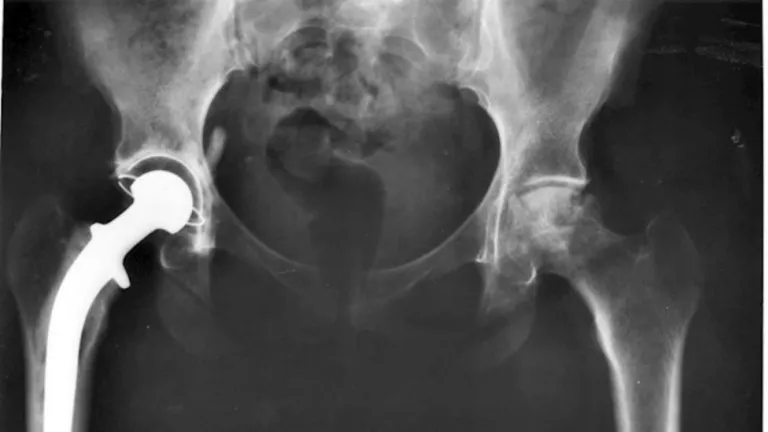

Hasta los 90 años se puede poner una prótesis de cadera